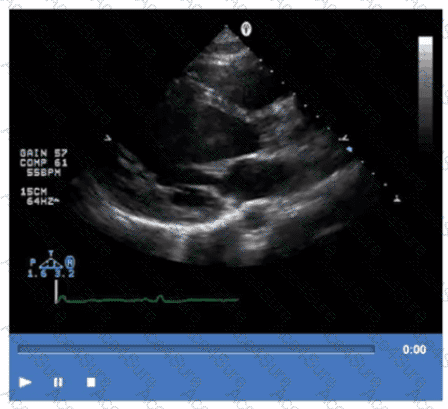

The video shows prominent trabeculations with deep intertrabecular recesses communicating with the left ventricular cavity, characteristic of isolated left ventricular noncompaction (LVNC). This congenital cardiomyopathy features a spongy myocardial appearance with thickened noncompacted layers.

Amyloidosis typically presents with thickened, bright myocardium but without prominent trabeculations. Sarcoidosis involves granulomatous inflammation, and apical hypertrophic cardiomyopathy shows localized hypertrophy without trabecular changes.